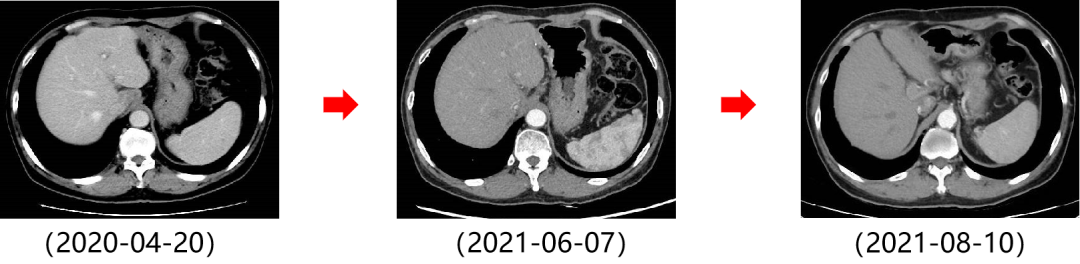

二 病例分享 专家简介 01 基本情况 患者:汪XX,男,63岁。身高 165cm;体重 65kg;体表面积 1.70m2;ECOG 1分。 主诉:反复解黏液血便3天。 对磁共振造影剂过敏,无食物、其他药物过敏史。既往史、个人史、婚育史、家族史均无特殊,无吸烟、饮酒史。 02 初诊病史 现病史:患者2017年3月初无明显诱因下解黏液血便,量中等,为鲜血,反复发作,无恶心、呕血、黑便、腹痛、腹泻、里急后重等不适。遂于2017年3月初就诊我院。 胸、腹、盆腔CT平扫+增强:乙状结肠肠壁明显增厚,肠腔狭窄,增强期强化明显;肝脏多发低密度病灶,增强期不规则强化,考虑乙状结肠癌伴肝脏多发转移。 03 治疗方案 【一线治疗】 2017-06-22 西妥昔单抗+FOLFIRI* Q2W×3 西妥昔单抗 900mg ivgtt D1; 5-氟尿嘧啶 0.6g iv D1,3.5g civ 48h; 亚叶酸钙 0.6g ivgtt D1; 伊立替康 280mg ivgtt D1。 第1疗程结束后黏液血便较前消失,过程顺利,耐受良好,无皮疹、腹泻等不良反应,治疗10疗程,疾病进展。 疗效评估-影像学(部分缓解,PR)。 2017-07-15 乙状结肠癌切除术* 手术记录:肿瘤位于乙状结肠,大小约4cm×3cm,未突破浆膜层,病灶周围可及数个稍肿大淋巴结,未及盆底种植结节。 手术过程顺利,术后恢复良好。 术后病理:(乙状结肠)中分化腺癌,浸润肠壁浆膜下层,两切缘阴性,未见脉管癌栓及神经束侵犯,LN 2/18(+) 2017-08-20 肝转移瘤切除术* 手术记录:肝脏肿瘤位于肝右叶,大小分别约2cm×1.5cm,1cm×1.2cm,其余肝表面未见异常结节,腹腔无腹水、无粘连。 手术过程顺利,术后恢复良好。 术后病理:(肝右叶病灶)中分化腺癌,结合临床病史,符合乙状结肠癌肝转移,肝组织切缘未见癌。 疗效评估-影像学(NED)。 2017-11-06 西妥昔单抗+FOLFIRI* Q2W×3 西妥昔单抗 900mg ivgtt D1; 5-氟尿嘧啶 0.6g iv D1,3.5g civ 48h; 亚叶酸钙 0.6g ivgtt D1; 伊立替康 280mg ivgtt D1; 过程顺利,无皮疹、腹泻等不良反应。每疗程后均予PEG-CSF预防性升白,耐受良好。 疗效评估-影像学(病情进展,PD1)。 胸、腹、盆腔CT平扫+增强:肝左外叶低密度灶,增强期不规则强化,结合病史,考虑结肠癌肝转移,余未见明显异常。 【二线治疗】 2018-03-06 肝左外叶肿瘤切除术* 术中探查见:肿瘤位于肝左外叶,质硬,边界不清,余肝脏表面未见异常结节灶,腹盆腔无腹水。 手术过程顺利,术后恢复良好。 术后病理示:(肝左叶)中分化腺癌,结合临床病史,符合结肠腺癌肝转移。 2018-04至2018-07 卡培他滨+奥沙利铂* Q3W×5 卡培他滨 1.5g BID D1-14; 奥沙利铂 200mg ivgtt D1。 过程顺利、耐受良好,无腹泻、神经毒性等不良反应。 疗效评估-影像学(病情进展,PD2)。 胸、腹、盆腔CT平扫+增强:肝尾状叶结节状异常密度灶,增强期不规则强化,结合病史,考虑结肠癌肝转移,余未见明显异常。 2018-07至2020-04 贝伐珠单抗+卡培他滨* Q3W×21 贝伐珠单抗 500mg ivgtt D1; 卡培他滨 1.5g BID D1-14。 过程顺利、耐受良好,期间曾出现II度腹泻,对症治疗后可恢复正常。无血压升高、出血、蛋白尿、手足皮肤反应。 疗效评估-影像学(最佳疗效,PR)。 疗效评估-影像学(病情进展,PD3)。 腹腔镜肝尾状叶切除术+腹腔粘连松解术* 术中探查见:肿瘤位于肝尾状叶,质硬,边界不清,余肝脏表面未见异常结节灶,腹盆腔无腹水。 手术过程顺利,术后恢复良好。 术后病理示:(肝尾状叶)中分化腺癌,结合临床病史,符合结肠腺癌肝转移。 2020-06至2021-09 贝伐珠单抗+卡培他滨* Q3W×16 贝伐珠单抗 500mg ivgtt D1; 卡培他滨 1.5g BID D1-14。 过程顺利、耐受良好,期间曾出现II度腹泻,对症治疗后可恢复正常。无血压升高、出血、蛋白尿、手足皮肤反应。 疗效评估-影像学(NED)。 疗效评估-影像学(NED)。 【三线治疗】 2021-12-16 西妥昔单抗+TAS-102* Q3-4W×2 西妥昔单抗 900mg ivgtt D1; TAS-102 60mg BID D1-5,8-12。 过程顺利、耐受稍差,期间出现II度骨髓抑制(三系减少),对症治疗后可恢复正常。无皮疹、输液反应等。 疗效评估-影像学(部分缓解,PR)。 04 治疗小结